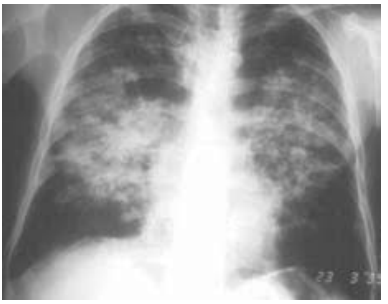

Paciente do sexo masculino, de 56 anos, trabalhou na lavoura a vida toda. Queixa de dispneia progressiva até aos moderados esforços há cerca de um ano, associado com tosse seca, perda de peso, com 5 kg nesse período. Ex-tabagista com uso de 25 maços/ano, parou há 15 anos. Ao exame, encontra-se em bom estado geral, afebril, eupneico, saturação periférica de oxigênio 95%, úlcera em mucosa oral. Feita biópsia da lesão oral, mostrando forma leveduriforme com múltiplos brotamentos, em forma de roda de leme. Traz raio X de tórax realizado.

Nesse caso, a principal hipótese diagnóstica para esse paciente é: